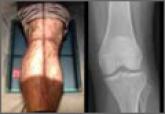

Tip of the Iceberg: Subtle Findings on Traumatic Knee Radiographs Portend Significant Injury